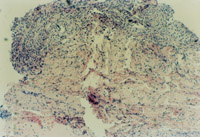

µÚ¶þ²½£º¹Ø±ÕÓúºÏ´´Ãæ

3-22 ¼ÌÐøÊ¹ÓÃMEBT/MEBO,ÉÕÉË´´ÃæÔÚÒ©²ã×÷Óñ£»£» £»£»£»£»£» £»¤Ï£¬£¬£¬ £¬ £¬£¬£¬£¬ÔÙÉúµÄƤ·ô×éÖ¯ÔÚÈâÑ¿´´ÃæÄÚ·ºÆðÉ¢Ô򵀮¤µã

3-23 ¶ÔÆä“Ƥµã”¾ÙÐÐ×é֯ѧ¼ì²é£¬£¬£¬ £¬ £¬£¬£¬£¬¸Ã×é֯Ϊ´ÓƤÏÂ×éÖ¯ÖÐÔÙÉú³öµÄ΢Ѫ¹Ü¡¢½ºÔ­×éÖ¯¡¢±íƤϸ°û×éÖ¯×é³ÉµÄÔÙÉúƤ·ô×éÖ¯ÍÅ

3-24 ¸Ã“Ƥµã”Öð½¥À©Õ¹ÎªÆ¤·ô×éÖ¯ÍÅ£¬£¬£¬ £¬ £¬£¬£¬£¬¸÷Ƥ·ô×éÖ¯ÍÅÏ໥ÈںϠ

3-25 ¸÷ÔÙÉúƤ·ô×éÖ¯ÍÅÈÚºÏΪ´óƬƤ·ô×éÖ¯

3-26 ¶Ô´óƬµÄÐÂÉúƤ·ô×éÖ¯¾ÙÐÐ×é֯ѧ¼ì²é£¬£¬£¬ £¬ £¬£¬£¬£¬Ö¤ÊµÎªÐÄÀíÐÔÆ¤·ôÈ«²ãÔÙÉúÐÞ¸´£¨É˺óµÚ49Ì죩